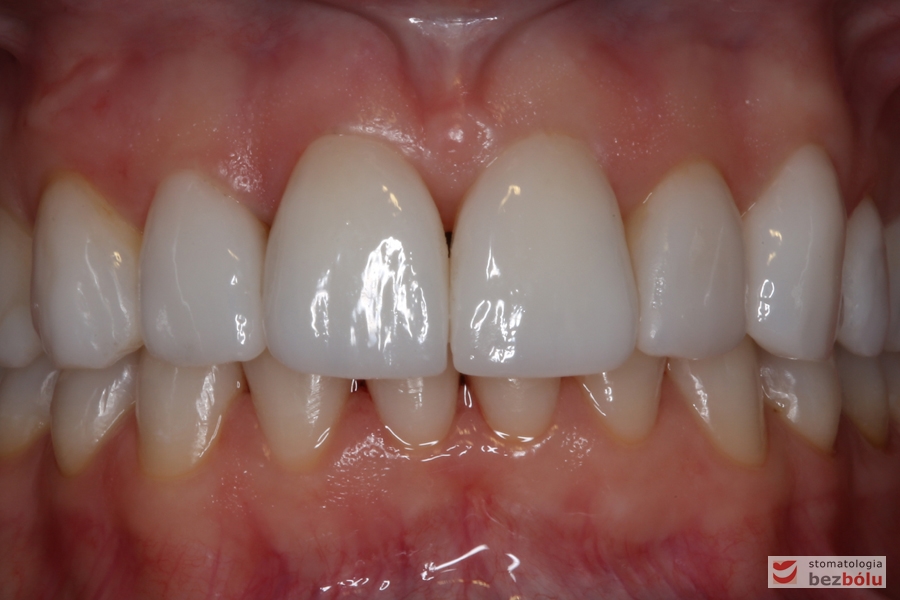

Ostateczne licówki caoceramiczne osadzone na zębach w odcinku przednim

Zmiana relacji długości do szerokości - zbliżenie do normy idealnych proporcji =80%

Zmiana relacji długości do szerokości – zbliżenie do normy idealnych proporcji =80%

Analiza uśmiechu po zacementowaniu pracy ostatecznej - en face

Analiza uśmiechu po zacementowaniu pracy ostatecznej – en face